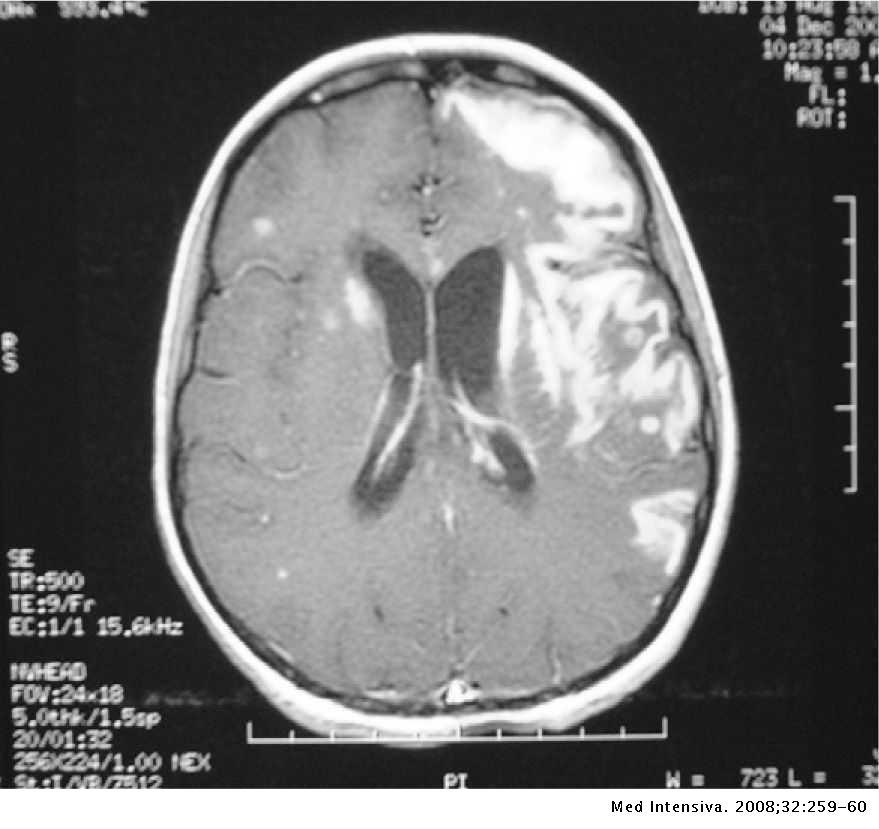

¿Qué vamos a encontrar en la TC de meningitis?

¿Cuál es el mejor estudio de imagen para la meningitis?

¿Cuál es el mejor estudio de imagen para las complicaciones de la meningitis?